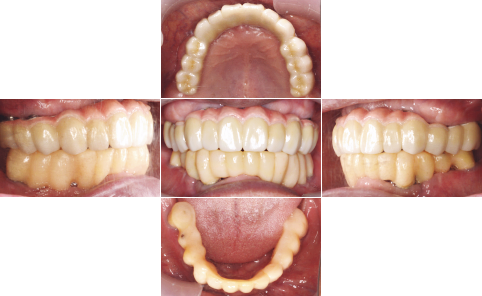

| 治療前 | 治療後 |

|---|---|

| 関西から通っている患者様です。 近々お嬢様の結婚式があるため、その前に上下共、All-on-4で治療して欲しいと来院されました。 右下親知らずは埋伏歯なので残してあります。 |